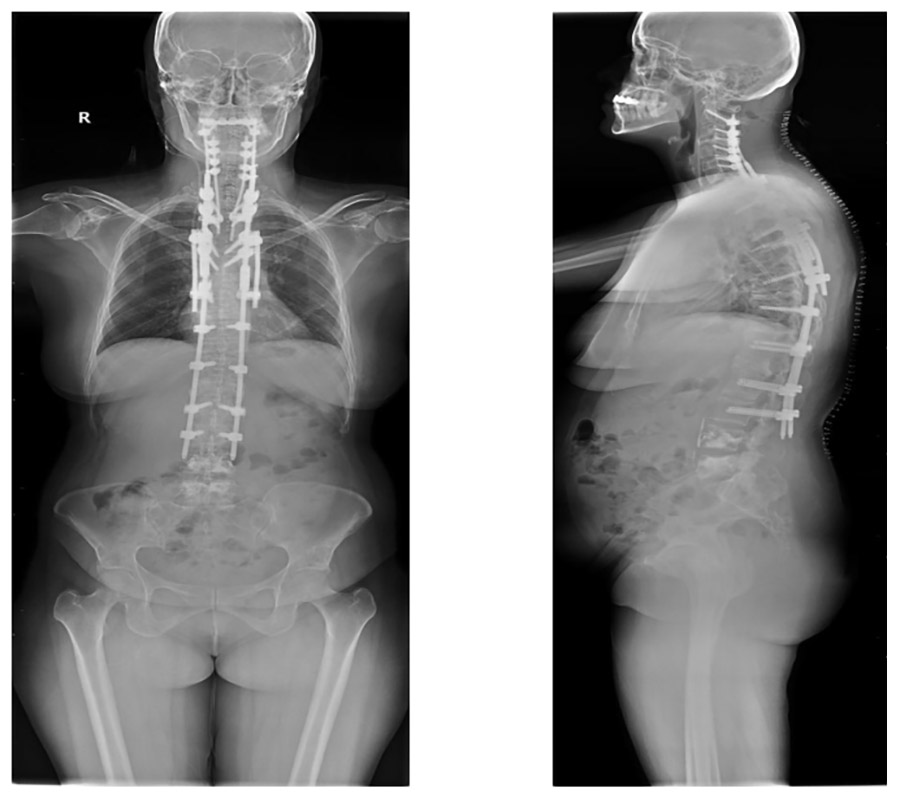

During surgery: The neck and back areas have open screw fastening, while the lumbar region has a closed screw fastening.

Post-surgery: The X-ray shows screw fixation (C2-L3 posterior instrumentation) and cementation (L4-5 vertebroplasty).